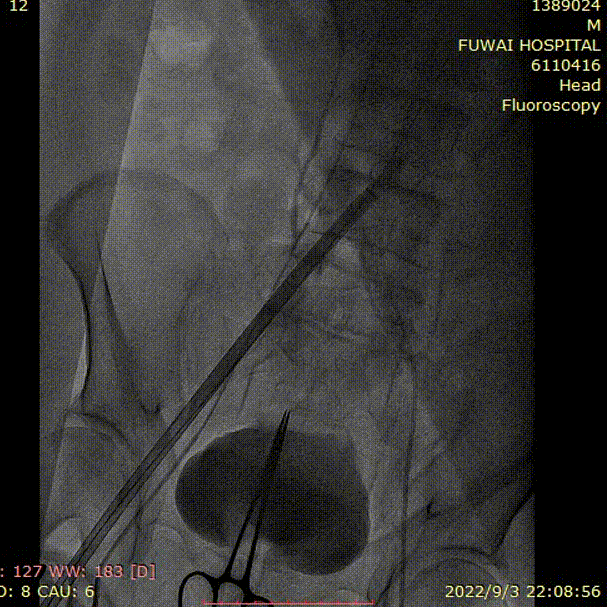

1、冠脉造影和抉择急诊PCI和急诊TAVR

左冠造影

右冠造影